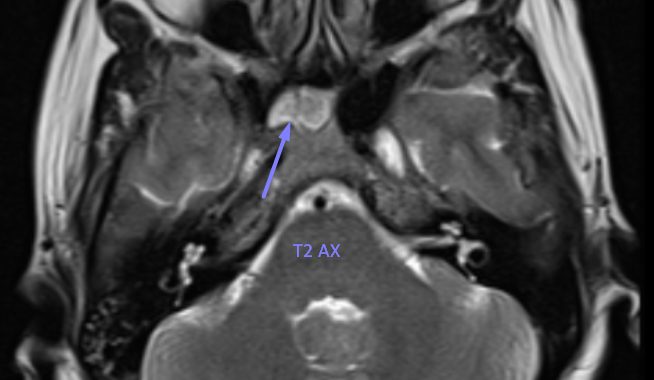

MR Findings:

T2: Central iso- to mildly hyperintense, with markedly hyperintense periphery (represents fibrous tissue or bone marrow interface).

MR signal characteristics:

Central iso-/hyperintense on T1 and

T2 → fat marrow

Peripheral hyperintense on T1 and T2 → fibrous tissue or bone marrow interface